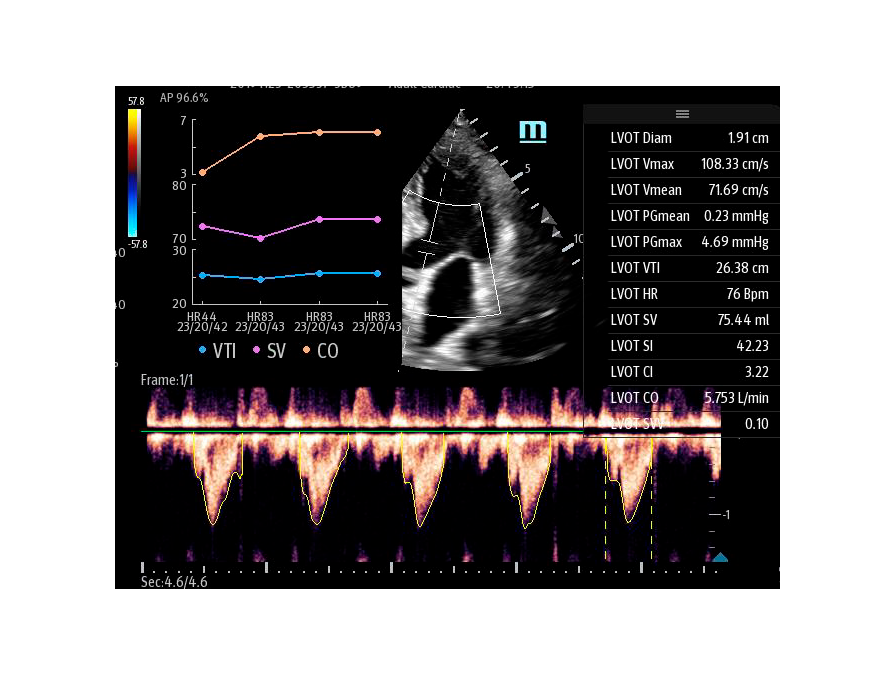

Автоматическая оценка потока выносящего тракта – Smart VTI

Чтобы использовать уравнение, нужно получить поток выносящего тракта левого желудочка в PW допплере — это достаточно кропотливая работа. В ультразвуковых системах Mindray Resona i9 эта задача решается автоматической оценкой потока выносящего тракта – Smart VTI.

Доктору остается получить 5-ти камерное сечение сердца и нажать одну кнопку на сенсорном экране. Прибор сам выберет расположение контрольного объема, получит спектрограмму и обведет спектр с расчётом всех показателей. Быстро и эффективно.